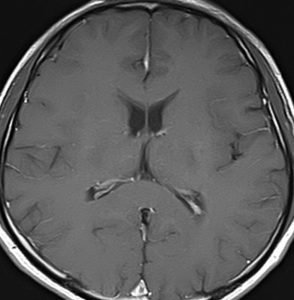

高齢者に発生したグリオーマです。左はガドリニウム増強MRIといいます。腫瘍の周囲が白く縁取られるように見えます。でも,右側のT2強調画像では,白く滲む部分が周囲に広がっています。

グレード3(かつての退形成性星細胞腫)かグレード4(膠芽腫),おそらく膠芽腫と「予想」できる画像です。確実ではないのですが,この予想は治療計画の上で重要なものです。